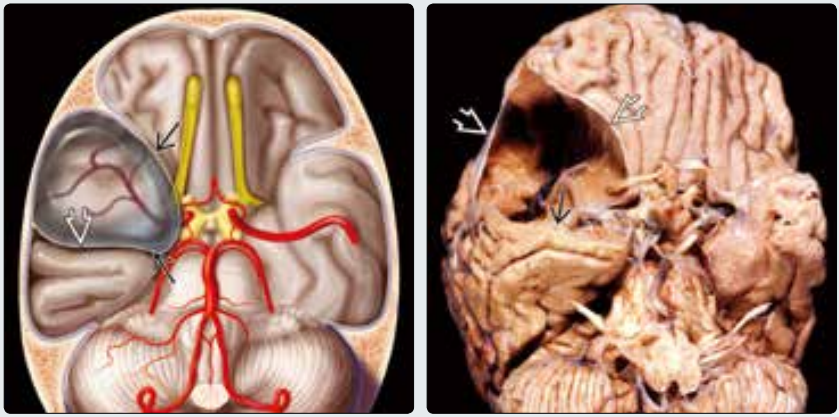

(左图)图示颅中窝蛛网膜囊肿,蛛网膜裂为两层→,包裹脑脊液。颅中窝扩大,骨质受压变薄。注意颞叶⇒受压向后移位。(右图)颏顶位显示尸检脑标本偶然发现颅中窝蛛网膜囊肿。注意“分层”的蛛网膜⇒包裹大量脑脊液(已排空)。颞叶受压向后移位→,颅中窝扩大(J.Townsend, MD 提供)